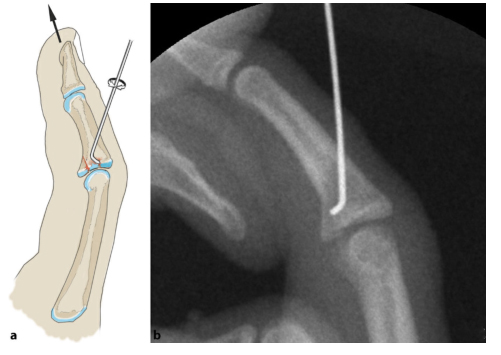

1. Схема модели чрескожной операции по уменьшению и фиксации стальными штифтами:

Применяют методику репозиции Хинтрингера и Эндера: сжатый костный фрагмент удаляют из костномозговой полости через дорсальное костное окно. Потяните вперед и согните проксимальный межфаланговый сустав на 20–30 градусов, чтобы уменьшить подвывих. Зафиксируйте костный фрагмент и проверьте устойчивость пальца в разогнутом положении. Если сохраняется тыльный подвывих средней фаланги, необходимо также заблокировать шкив, в котором в фалангу вводится стальной штифт.

Разрез производят дорсально от средней фаланги в сухожильном треугольнике. При продольном вытяжении (стрелка) палец сгибается на 20–30°. Просверлите отверстие через разрез, наклонив его проксимально (изображение ниже).

Согните один конец 1-миллиметровой проволоки на 30°, чтобы придать ей форму хоккейной клюшки. Затем его вводят в костномозговую полость через просверленное отверстие.

Сокращение суставной поверхности и подвывих при вытяжении. Изогнутая проволока занимает примерно четверть площади соединения. Проксимальная суставная поверхность играет здесь вспомогательную роль.

После репозиции через сухожилие сгибателя с ладонной стороны проводили спицу Киршнера диаметром 0,6 мм для фиксации костного фрагмента.